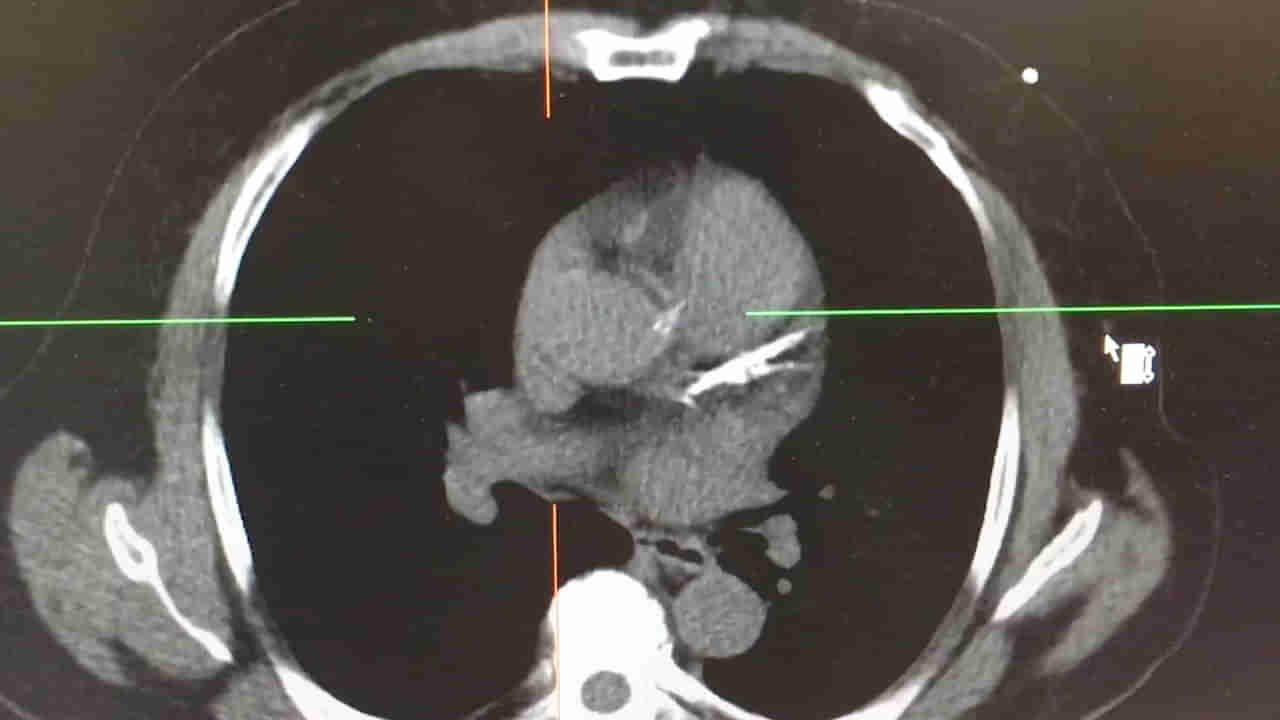

వైద్యులకు మొదటిగా ఆమె పరిస్థితి అర్ధంకాలేదు. అయితే చిన్నారికి CT స్కాన్ చేసిన అనంతరం ఆమెకు రెండోసారి గుండెపోటు వచ్చిందని తేల్చారు. ఆ చిన్నారి పరిస్థితి చూసి వైద్యులు సైతం ఆశ్చర్యపోయారు. ఆ సమయంలో ఎల్లామే కాటెకోలమినెర్జిక్ పాలిమార్ఫిక్ వెంట్రిక్యులర్ టాచీకార్డియా(CPVT) అనే అరుదైన వ్యాధితో బాధపడుతున్నట్లు గుర్తించారు. దీని వల్ల హార్ట్ రేటులో హెచ్చుతగ్గులు ఉండటమే కాకుండా గుండెపోటు వంటి వ్యాధులు కూడా వచ్చే అవకాశం ఉందట.